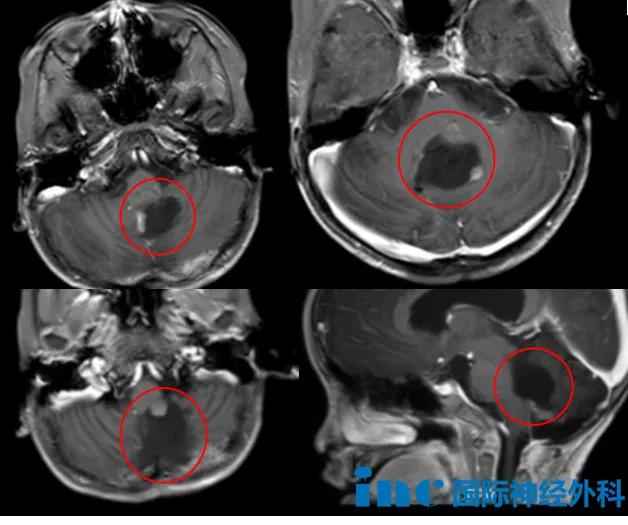

年仅5岁的布布患有后颅窝室管膜瘤,此前已历经两次开颅手术和一次质子治疗,但肿瘤再次复发。年龄小、体重轻、血容量低,加之而肿瘤又深深嵌入脑干背侧,且呈现多发性生长。术中发现的情况比术前影像显示的更为复杂——MRI增强扫描中仅显示为3处强化灶,但实际开颅后,发现存在更多未显影的肿瘤。这一仗,并不好打……

5岁的布布,自2023年因走路不稳被发现颅内肿瘤起,便踏上了这条崎岖之路。同年9月,他接受了第一次后颅窝肿瘤切除手术,术后病理诊断为室管膜瘤。然而,病魔并未远离,2024年5月肿瘤复发,再次手术后的病理结果升级为更具侵袭性的间变性室管膜瘤(WHO 3级)。手术带来了严重的神经功能影响——斜视、四肢无力、吞咽困难、言语迟缓……

一个个难题接踵而至。在完成质子放疗后,近期复查的影像疑似再次复发:术区边缘出现可疑结节,并与生命中枢延髓紧密粘连。